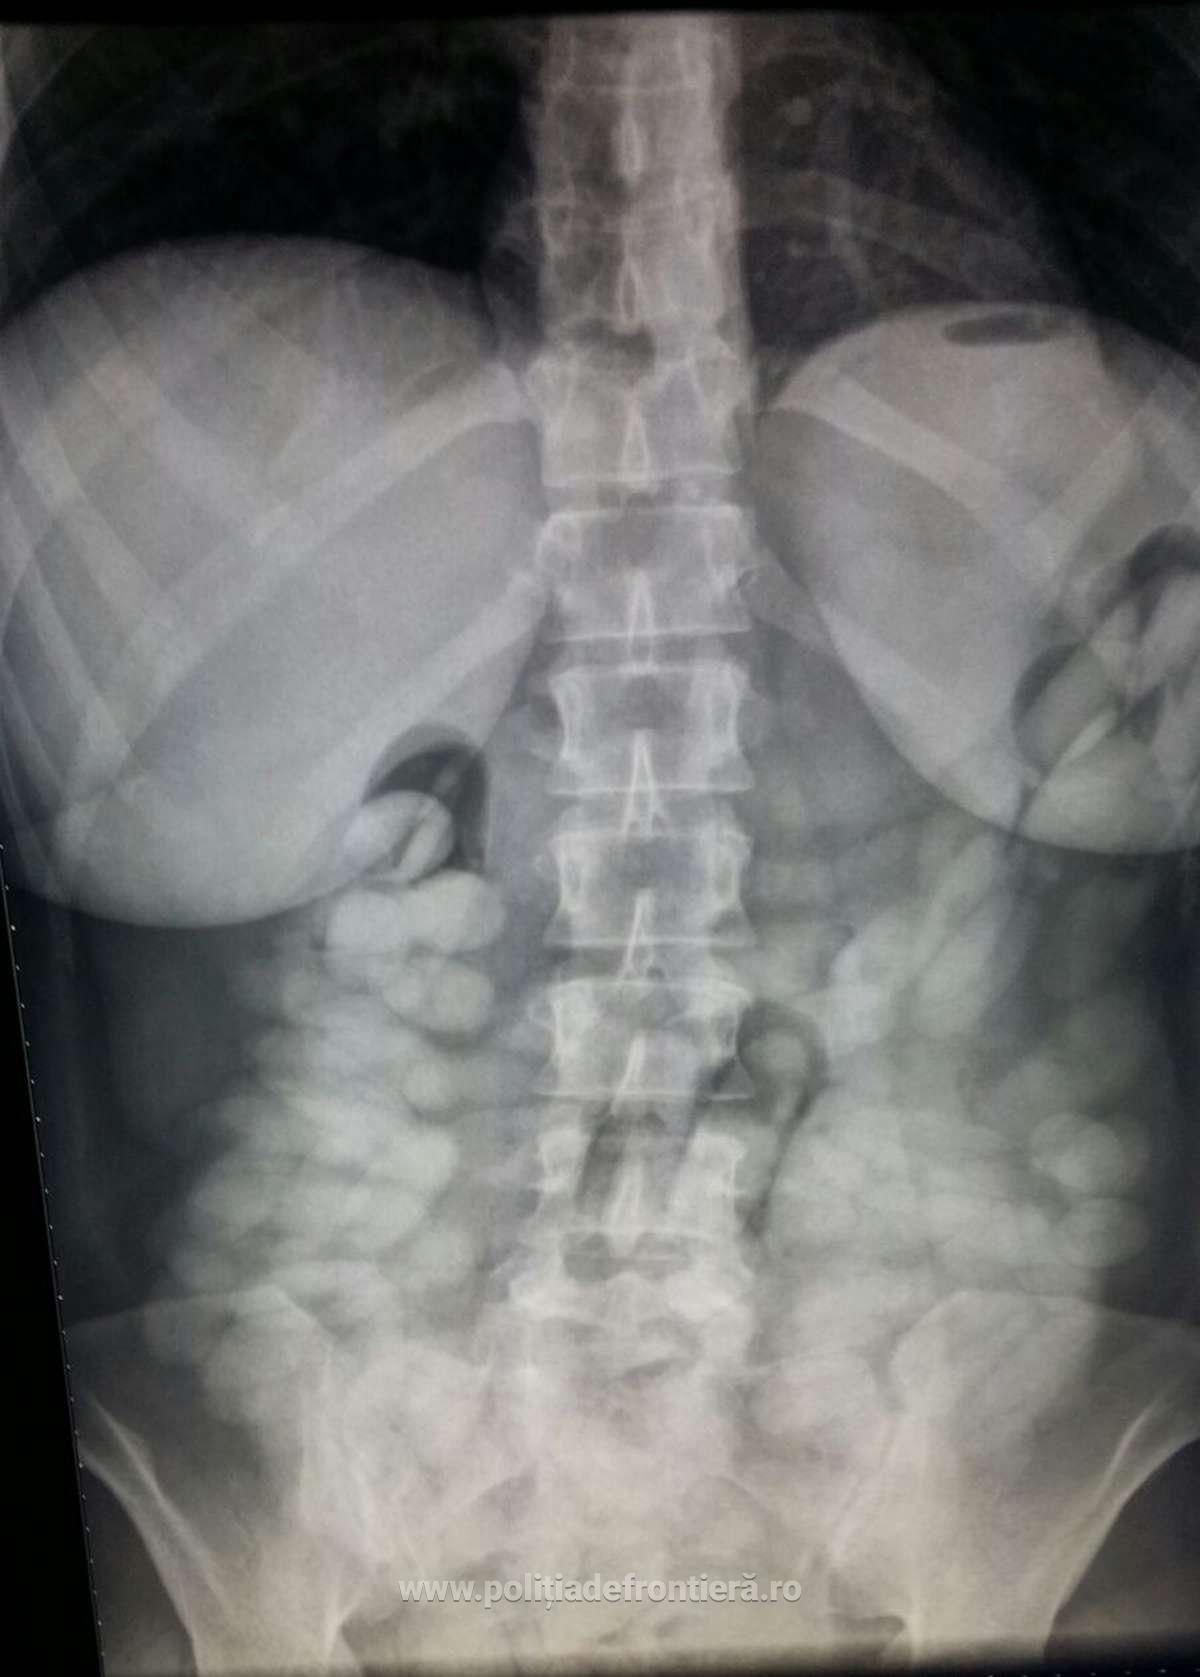

Existând suspiciuni că transportă substanţe interzise, persoanele în cauză au fost supuse unui control cu raze X, cu aparatul aflat în dotarea Poliţiei de Frontieră din cadrul Aeroportul Internaţional Henry Coandă.

Cu această ocazie s-a constatat că două dintre persoane, Verice R. şi Weslley L. aveau zeci de capsule ingerate în stomac.